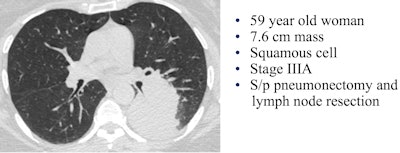

Image courtesy of Dr. Hanna Milch.To assess risk, the group created a standardized "Bronx score" that estimates lung cancer probability similar to the BI-RADS model for breast cancer. A Bronx score of 1 or 2 means the CT was negative or there were benign findings, resulting in a follow-up screen in one year. A score of 3 or 4 means that detected nodules or opacities require a shorter-term follow-up, and a score of 5 means a high suspicion of malignancy. Radiation dose was recorded for each scan.

In all, 320 of the referred patients were screened for lung cancer, and nine had a score of 5 on the Bronx score, eight of whom went on to receive a histology-proven lung cancer diagnosis. The ninth patient's CT scan was highly suspicious for malignancy, but the patient has not yet had a tissue confirmation.

Of the eight patients with confirmed lung cancer, just two had adenocarcinomas, which are more often curable, and only one patient had stage I disease.